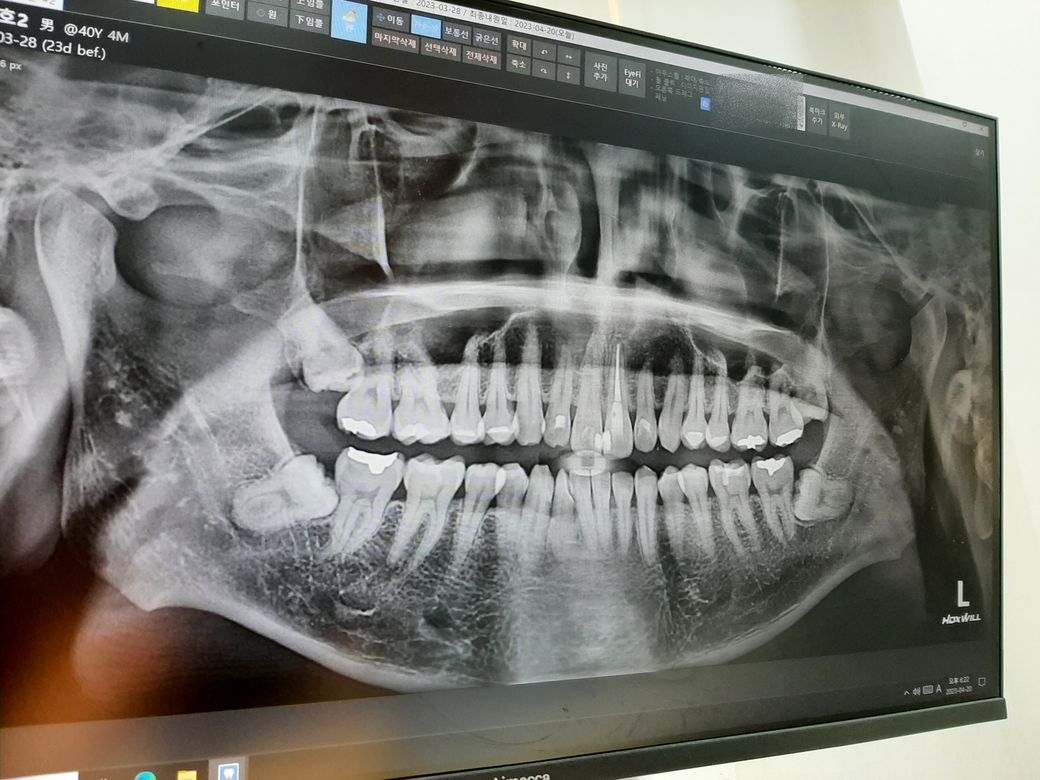

전체 사진입니다. (현재 위의 사랑니는 모두 발치했습니다.)

왼쪽 아래 사랑니 (사진은 클릭하면 커집니다.)

발치한 치과에서는 처음에 아래쪽 사랑니가 더 급하다는 식으로 이야기했던 거 같은데 순서는 위에 2개 발치하고 아래는 경과를 더 지켜보고 나중에 발치하자는 식으로 마무리하셨습니다.

3. 왼쪽과 오른쪽 중에 지금 당장 치료해야 할 부분이 있나요?

-엑스레이 상으로는 크게 문제가 잇어 보이진 않습니다.